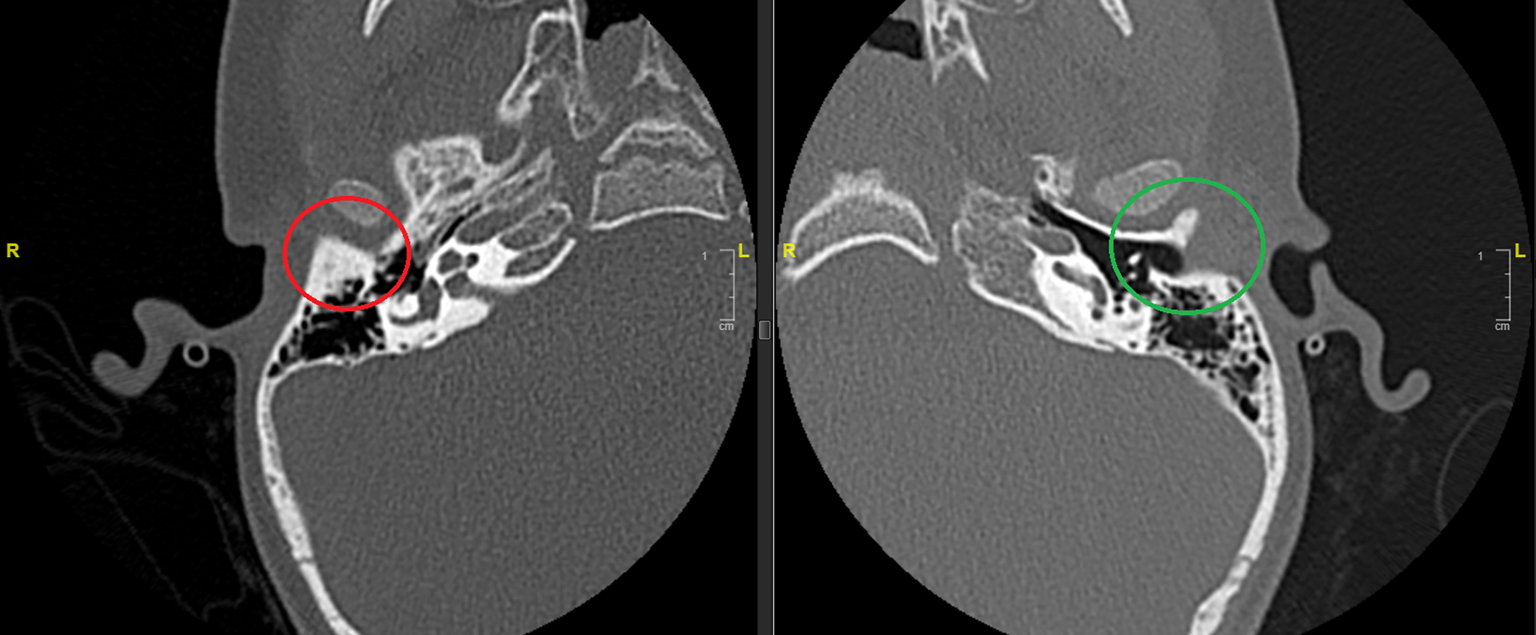

Die nachgewiesenen Dysplasien treten dabei unterschiedlich häufig auf. In etwa der Hälfte der Fälle findet sich bei Patienten mit höhergradigen Ohrmuscheldysplasien oder Gehörgangsatresien ein verminderte Mastoidpneumatisation, in fast 90 % der Fälle ist hier auch das Volumen der Pauke reduziert [25]. Ossikeldysplasien sind ebenfalls häufig. Oft zeigt sich ein dysplastisch verklumpter Hammer-Amboss-Komplex oder nur rudimentär angelegte Ossikelanteile. Der Stapes wird von allen Ossikeln (mit 31 % bei höhergradigen Fehlbildungen) noch am häufigsten angetroffen. Das runde Fenster scheint in 90 % der Fälle offen, während das ovale Fenster bei 40 % der Patienten mit Gehörgangsatresien und höhergradigen Ohrmuscheldysplasien verschlossen ist (Abb. 8). Der Verlauf des N. facialis ist bei mehr als 3 Vierteln der Patienten mit höhergradigen Dysplasien verändert. Im Mittelohr wird dabei oft eine Verlagerung nach kaudal, im Mastoid hingegen nach ventral beobachtet (Abb. 9). Der Austritt aus der Schädelbasis ist im Rahmen einer Gehörgangsatresie häufig weiter kranial. Entsprechende Kenntnisse sind zur Vermeidung intraoperativer Komplikationen von höchster Wichtigkeit. Assoziierte Fehlbildungen des Innenohrs wurden bis auf diskrete Veränderungen des lateralen Bogengangs in einer Analyse von Siegert et al. nicht beobachtet [25]. Diesbezüglich wird erneut auf die Bemerkungen im Abschnitt „Embryologie“ hingewiesen.

Abb. 9

Aberranter Verlauf des N. facialis bei Gehörgangsatresie. Im dargestellten Beispiel rechts eine Verlagerung des Nervs nach lateral. (Quelle: Abb. 8 S. 25 in [26])